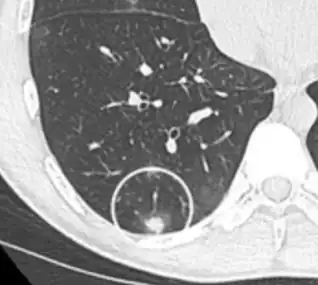

subpleural nodule.[9]

Round well-delineated solid lung nodule with smooth border.[9]